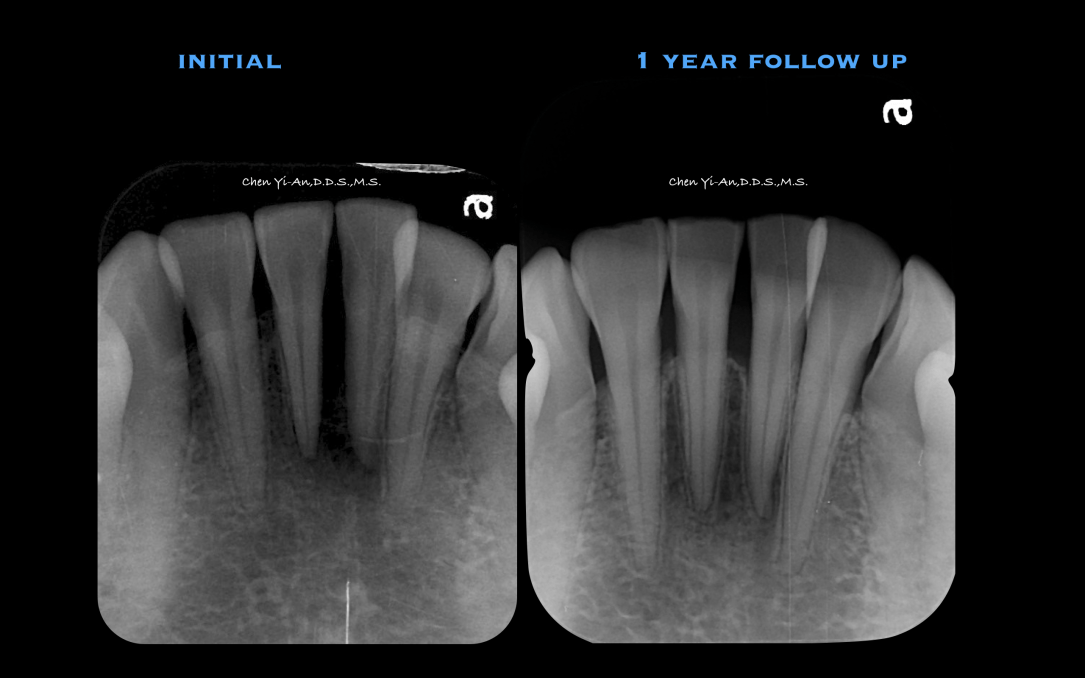

關於植牙,身為一個牙周病專科醫師,還是必須強調『植牙功能是用來取代缺牙,而非真牙』,需要被拔牙的牙齒,在陳醫師手上,總是要仔細評估再評估。在這邊跟大家分享的全口重建案例:楊先生患有牙周病,初診諮詢全口好幾顆牙齒發炎冒膿,搖搖欲墜,經過牙周治療之後,除了移除殘根碎片之外,一顆自然牙也沒有少!牙周治療後,才進行植牙,恢復齒列。回復齒列之後,楊先生學會正確口腔衛生照顧方式,後續也每半年安排定期回診保養,以確保植牙能在口中「長治久安」。

如果植牙後能夠保持口腔清潔衛生,以及定期接受牙科檢查,在維護良好的情況下,植牙是可以長期使用,因此成為重要的缺齒修復方法。